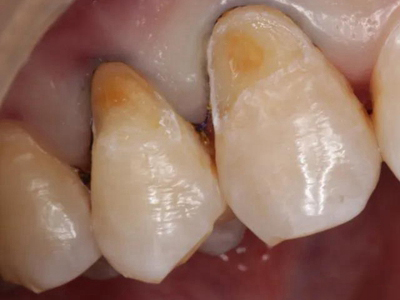

酸蚀症牙齿缺损不平整图

酸蚀症患者的牙齿会发生缺损,轻度时仅表现为牙齿尖端凹凸不平,有少量骨质缺失,缺损处有黄褐色至红褐色斑点,该病可能是长期接触外源性酸性物质而致病。